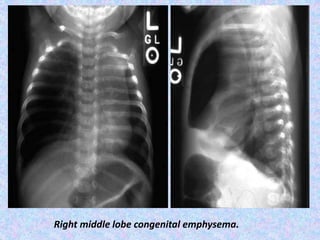

Right middle lobe congenital emphysema.

Congenital Lobar Emphysema. CLEalmost always involves one lobe, with rates of occurrence as follows: Left upper lobe - 41% Right middle lobe - 34% Right upper lobe - 21% Congenital lobar emphysema has 2 forms: Hypoalveolar (fewer than expected number of alveoli) Polyalveolar (greater than expected number of alveoli) X-Ray shows unilateral –translucency. CT Scan shows hyperinflation of one or more lobes with attenuated pulmonary vasculatures, compression atelectasis of the adjacent lung and mediastinal shift.

Right middle lobecongenital emphysema.